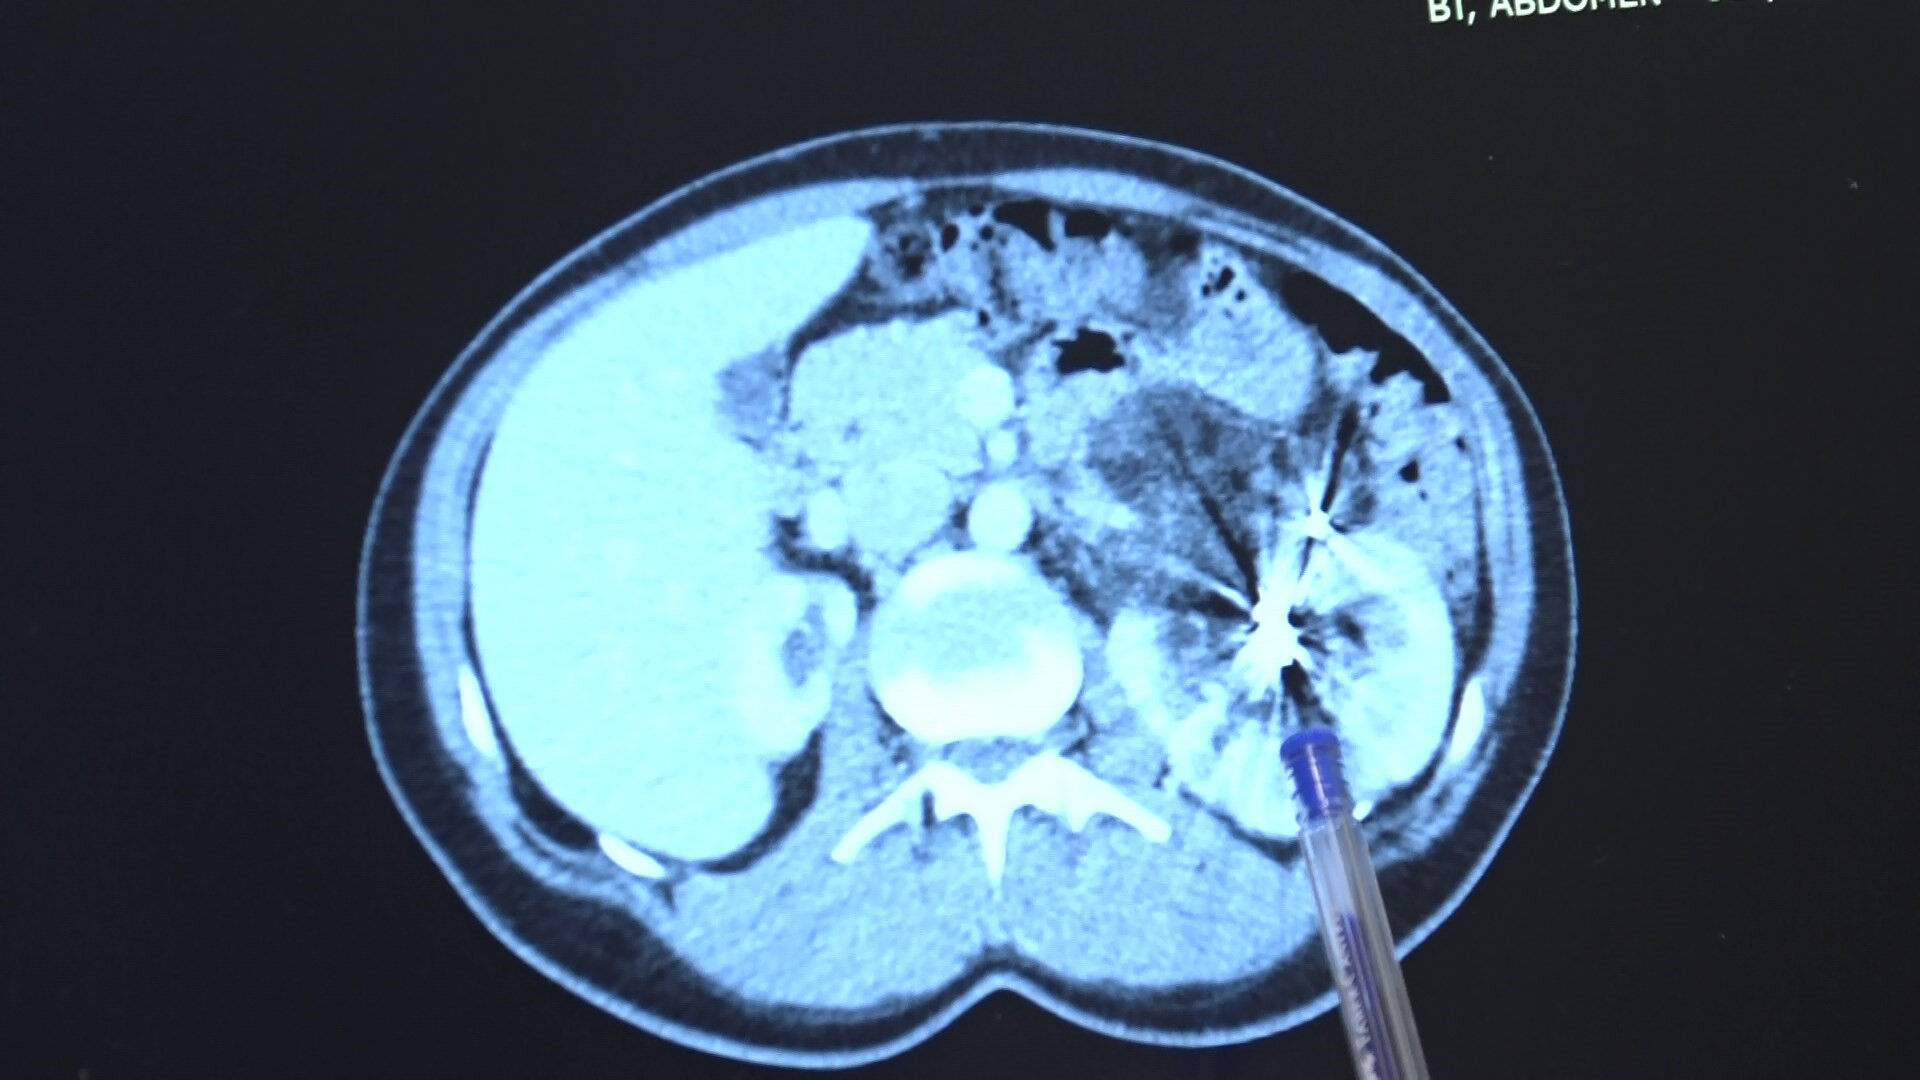

MR sonuçlarını inceleyen doktor, bir böbreği çok küçük olan hastanın doğduğu günden bu yana tek böbrekle yaşadığını belirledi.

Yıllar sonra tekrar MR çektiren hastanın tek böbreğinde bu sefer bir kitle olduğu görüldü.

Kitlenin iyi huylu olduğu söylenmesi üzerine iki sefer embolizasyona işlemi yapıldı. Fakat kitle büyümeye devam etti.